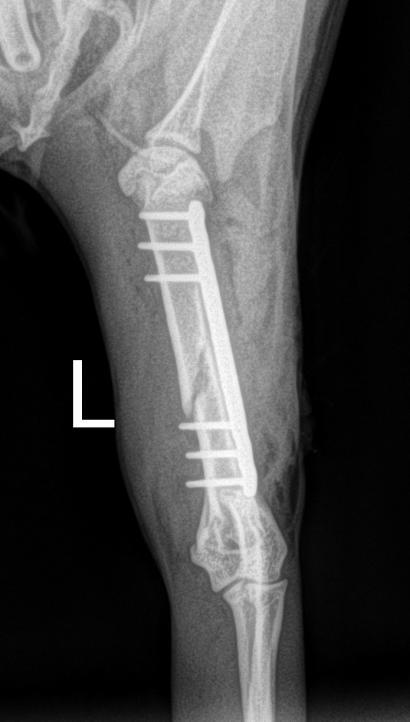

Day 1: He had to fix a humerus spiral fracture (left) with a LeiLOX bridge plate. Furthermore, he diagnosed a femur transverse fracture. Dr. Sonntag then used a 7-hole LeiLOX plate to repair this fracture, and do several emergency soft tissue surgeries.

(Surgery time: 1:15 hours)

“Especially remarkable are the short surgery times.

On this aspect, the LeiLOX System has once again proven one of its many important capabilities.

With conventional plates, this would not have been possible. LeiLOX was the reason why I could repair everything in ONLY two surgeries.”